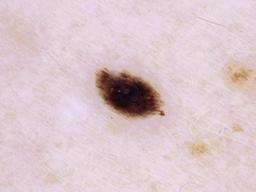

5. Melanoma (mel)